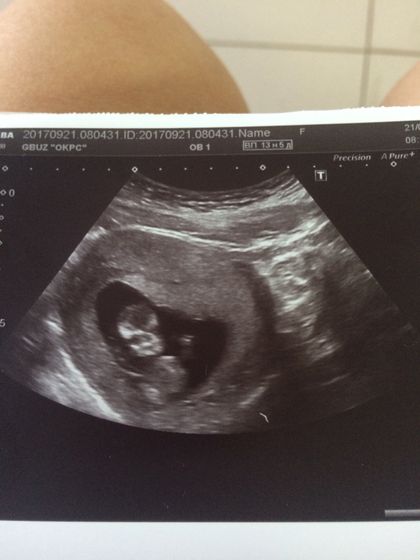

Еду утром, волнуюсь как первоклассница? лишь бы все хорошо было. Сначала просто по животику смотрели водили, потом все-таки внутрь залезли. Узист начала меня то покашляйте, то с боку одного на спину, то с другого, ворочает, я уже волноваться начала ? потом данные ещё продиктовала экран мне поворачивает и показывает… а там на месте секунды не лежит постоянно руками-ногами машет, лицо вообще сначала закрыл(а) носовую кость померить не могли минут 7-10??? говорит узист ооооочень активный ребёнок и срок уже как оказывается 12 и 5, а не 11 и 3… вот так, ждём результат крови. По узи тьфу-тьфу все хорошо без отклонений… еле-еле поймали пока руки от лица оторвал(а).

Такое ощущение что смотрит и улыбается )